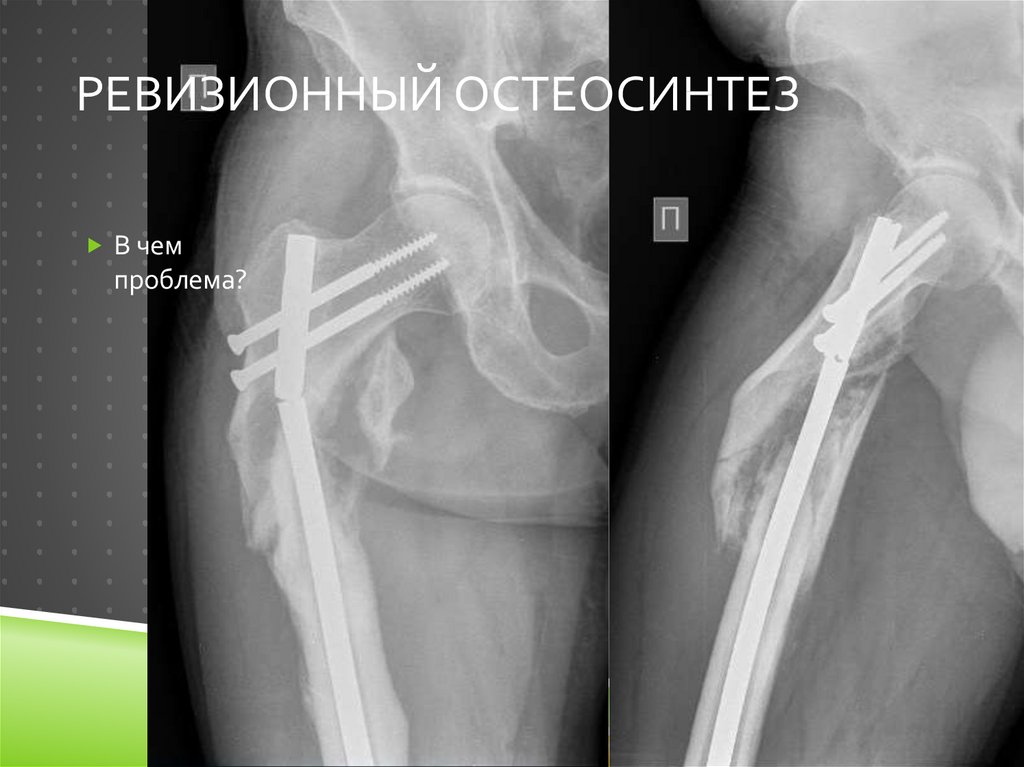

Ревизионный остеосинтез